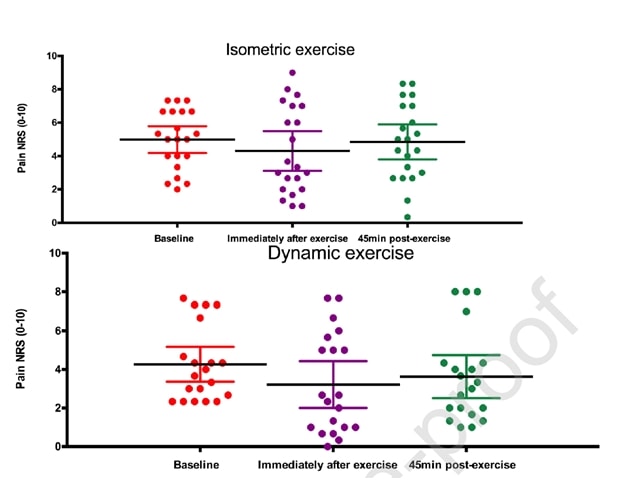

里奥等人 (2015) 当他们对 6 名患有髌骨肌腱病的排球运动员进行交叉试验时,掀起了一股风潮。 他们的研究结果令人吃惊,所有运动员的疼痛都立即减轻,从 NRS 平均 7/10 减轻到 0,6 名运动员中只有一人在等长收缩后至少 45 分钟内仍感到 1- 的疼痛。 他们采用的方案是在伸腿机上进行 5 组 45 秒的收缩,用力达到最大自主用力的 70%。 他们还发现,等距运动能够减少大脑皮层的抑制作用,使力量增加 19%。 他们将等长干预与等张干预进行了比较,结果等长干预组无法达到等张干预组的效果:

同一作者还在两年后对跳跃运动员进行了赛季内跟踪研究(Rio et al. 2017)中,他们对等长程序和等张程序进行了比较。 在这项研究中,两组的结果差异较大,等长组的即时疼痛减轻程度更高:

最近的一项研究 霍尔登等人 (2019)也研究了等长运动对髌骨肌腱病的影响,但没有发现任何镇痛效果:

图自 Holden 等人 (2019)